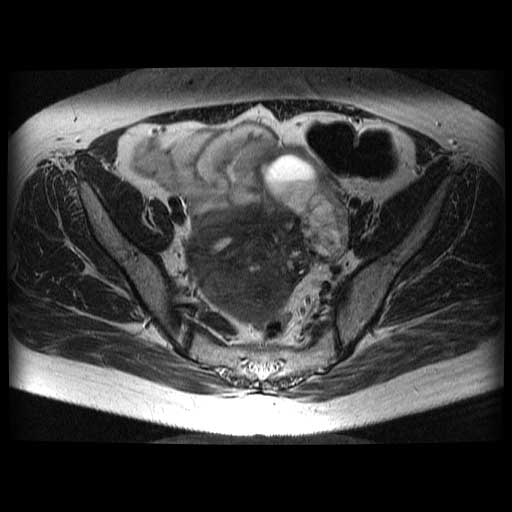

No.58症例6:47歳、女性 1G1P

41歳時に月経困難症にて当院受診、MRIにてendometriosis、adenomyosis、myoma uteriと診断される.GnRH agonist、低容量ピルを投与されていたが、1年半前より休薬していた.

定期受診にて左卵巣腫大を疑われ、精査加療目的にて入院.

CA19-9 43.9(<37)、CA125 375.2(<35)